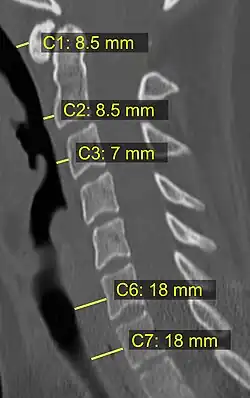

Na tomografia computadorizada ou radiografia, uma fratura cervical pode ser visualizada diretamente. Além disso, sinais indiretos de lesão pela coluna vertebral são incongruências das linhas vertebrais,[6] e/ou aumento da espessura do espaço pré-vertebral:[7]